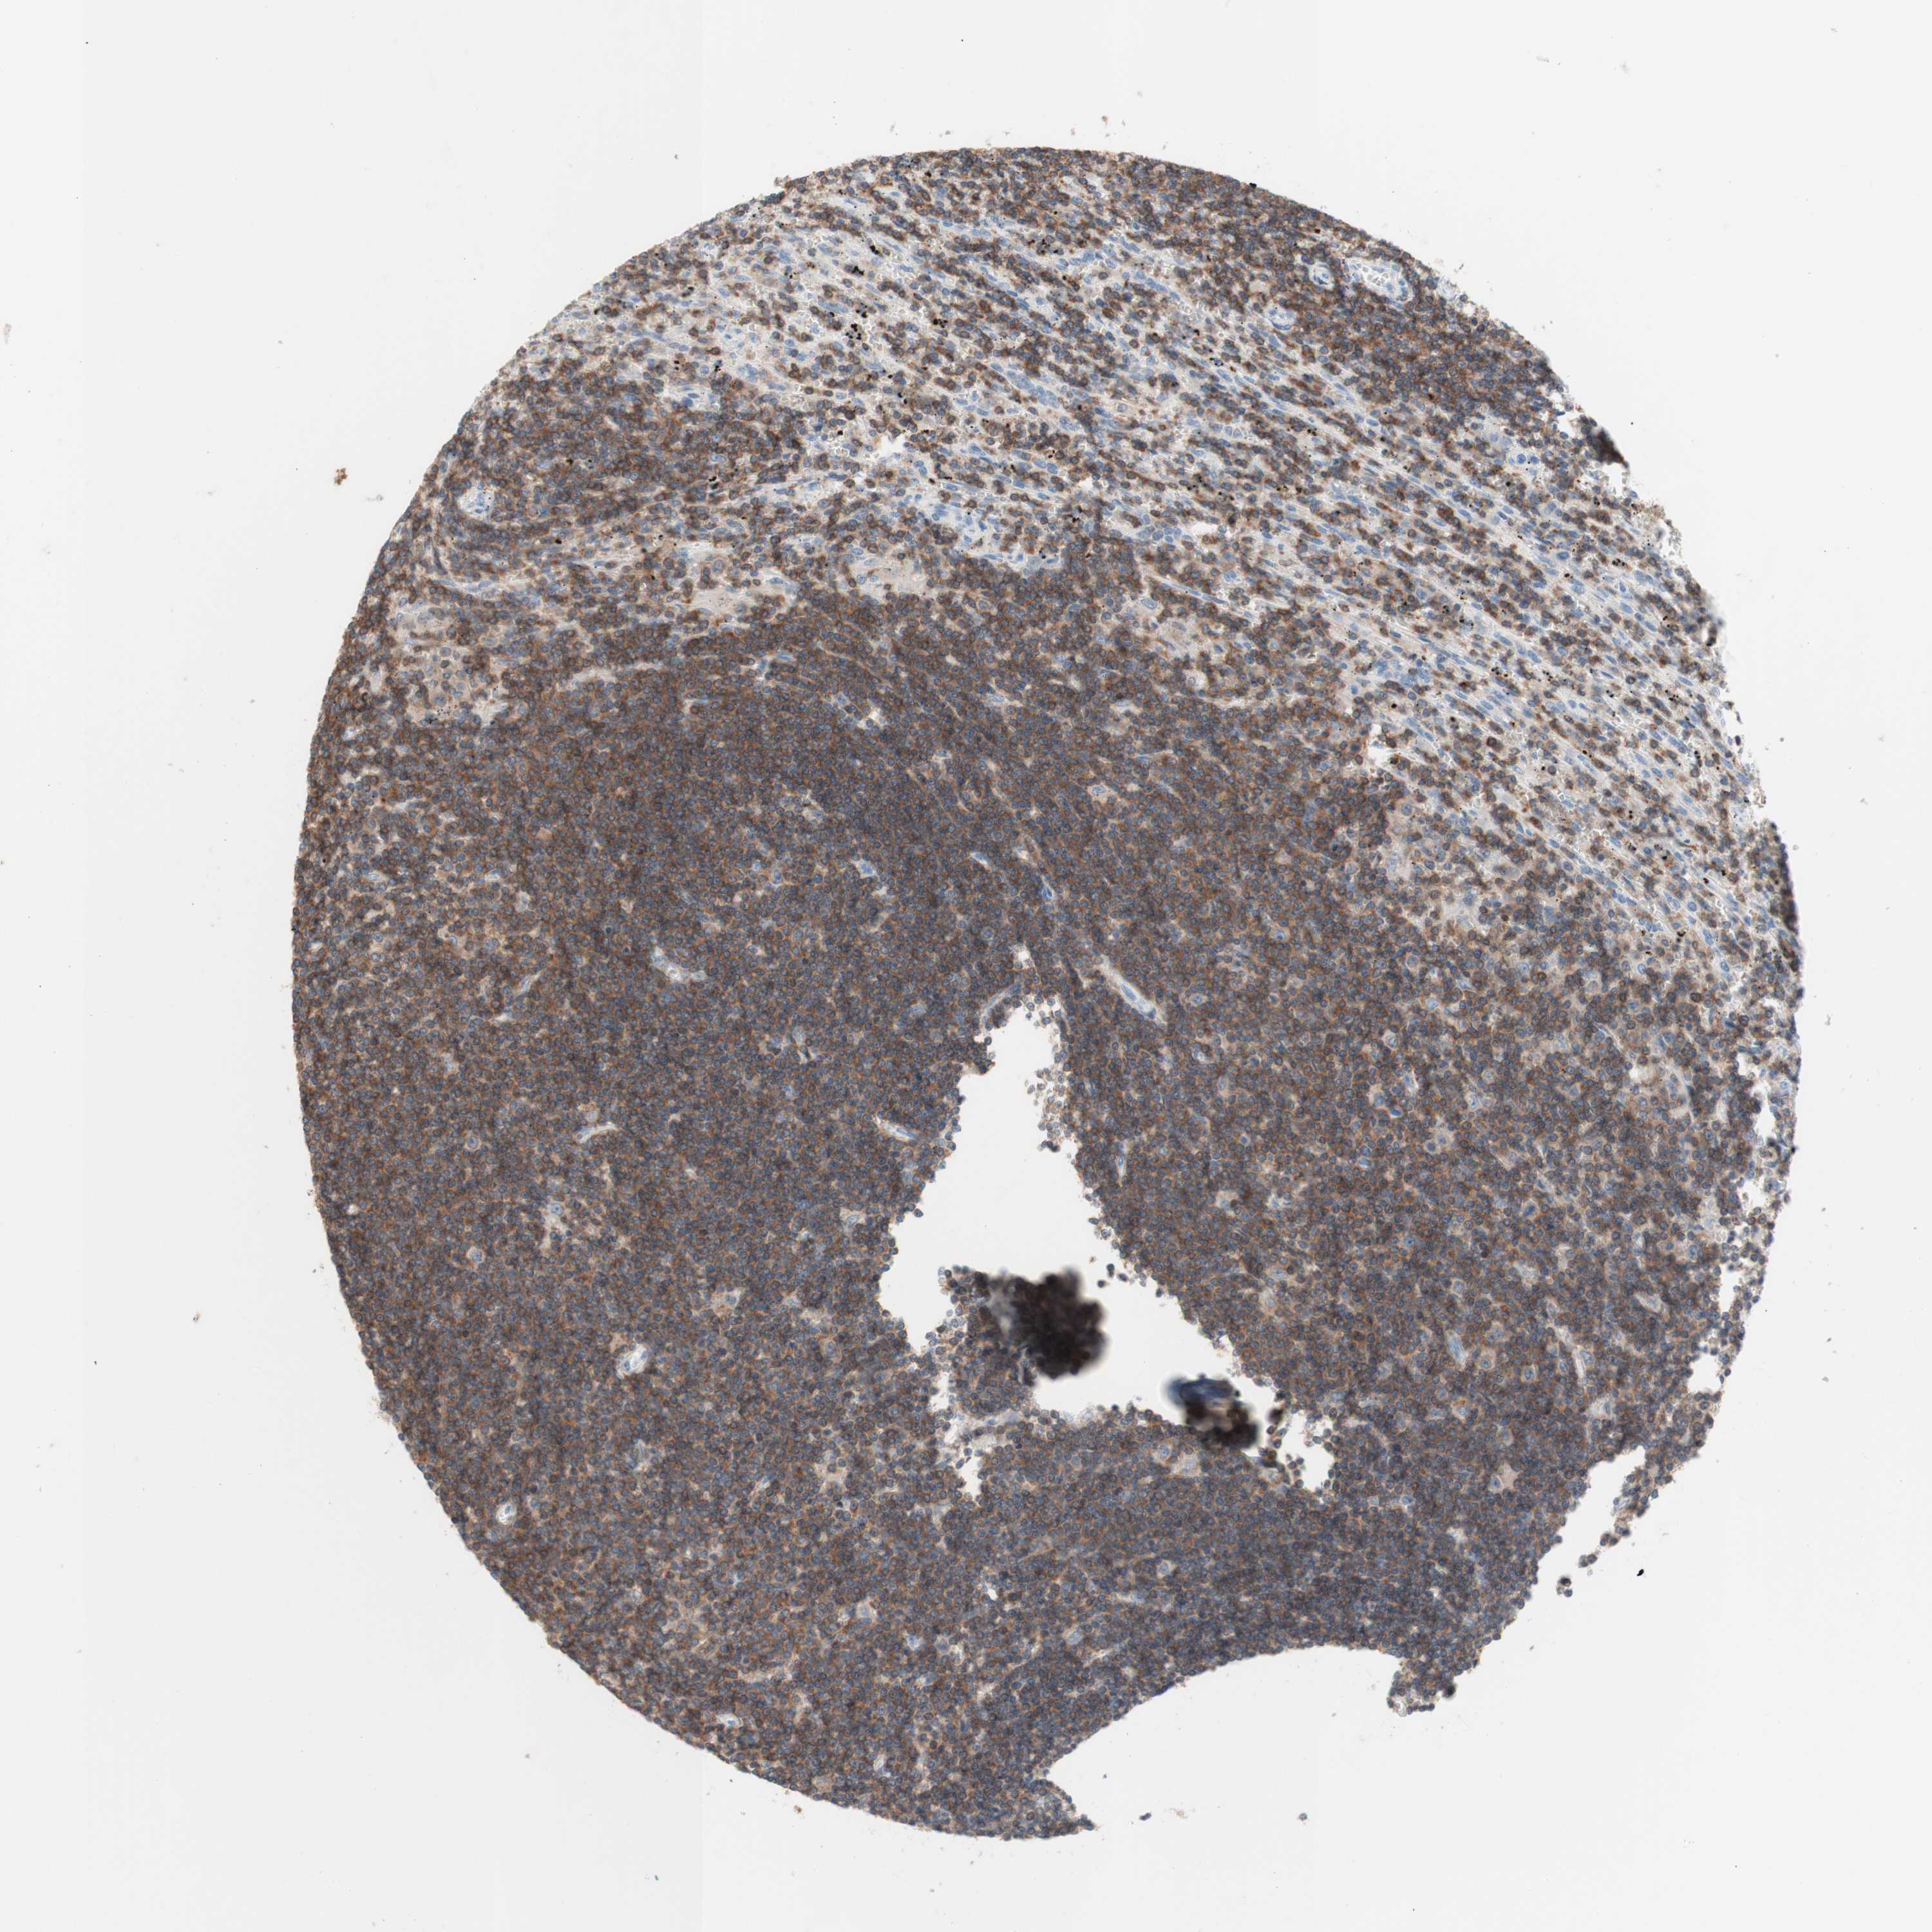

CANCER LYMPHOMA Show tissue menu

LYMPHOMA - Protein expressioni

A mouse-over function shows sample information and annotation data. Click on an image to view it in a full screen mode. Samples can be filtered based on level of antibody staining by selecting one or several of the following categories: high, medium, low and not detected. The assay and annotation is described here.

Antibody stainingi

Antibody staining in the annotated cell types in the current human tissue is reported as not detected, low, medium, or high, based on conventional immunohistochemistry profiling in selected tissues. This score is based on the combination of the staining intensity and fraction of stained cells.

Each image is clickable and will lead to virtual microscopy that enables deeper exploration of all samples and also displays staining intensity scores, fraction scores and subcellular localization as well as patient and tissue information for each sample.

Antibody HPA011039

Staining

High

Medium

Low

Not detected

Intensity

Strong

Moderate

Weak

Negative

Quantity

>75%

75%-25%

<25%

None

Location

Nuclear

Cytoplasmic/membranous

Cytoplasmic/membranous,nuclear

Hodgkin's disease, NOS

Malignant lymphoma, non-Hodgkin's type, Low grade

Malignant lymphoma, non-Hodgkin's type, High grade